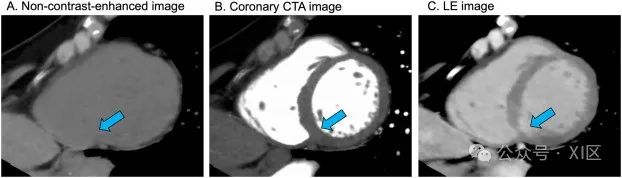

左心室造影通常进行定性评估。对图像进行主观观察时,将平扫、CCTA和LE图像的左心室短轴图像对齐非常有用。观察LE图像时,宜使用窄窗口设置以突出对比度。此外,应根据所使用的管电压和VMI能量水平适当调整窗口设置。例如,当使用120 kV 的管电压时,应使用60-80 HU的窗中心和80-110 HU的窗宽。此外,在调整窗值设置时,还应考虑CT扫描仪的特性和图像质量水平。左心室下壁很容易受到来自膈肌的条纹伪影的影响,因此在解读图像时应小心谨慎。

LE 图像的推荐视觉观察方法。对图像进行主观观察时,将平扫(A)、CCTA(B)和 LE(C)图像的左心室短轴图像对齐非常有用。通过对比 LE 图像和 CCTA 图像,可以评估 LE 病变的范围(箭头)。平扫图像可确认LE病变不是钙化。Ohta等人将LGE-MRI作为参考标准,报告40 keV VMI和碘特异性图像在检测LE方面的敏感性分别为94.3% 和97.1%,特异性分别为88.9%和88.9%。Oda等人的研究表明,50 keV VMI对LE的肉眼检测的观察者间一致性非常好,其κ值(κ,0.87)高于标准 120 kV(κ,0.70)和碘特异性图像(κ,0.83)。50 keV的VMI(κ,0.90)和碘特异性图像(κ,0.87)与LGE-MRI检测LE病变的一致性非常好,而且优于标准120 kV成像(κ,0.66)。LE的范围可以用绝对参数计算,并根据以下公式计算左心室总质量的百分比: